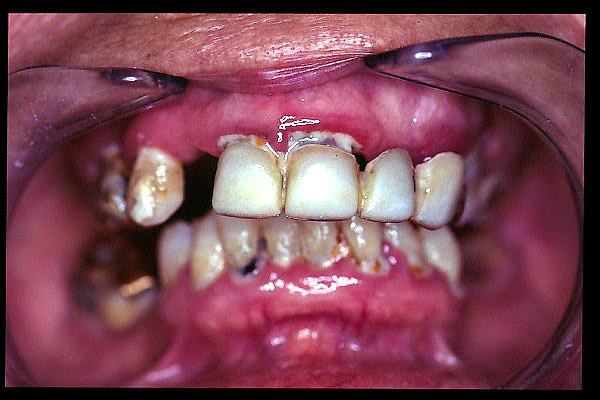

CM Prótesis fija, placa bacteriana, enfermedad periodontal y caries